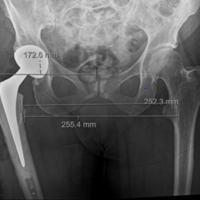

During the hospital stay, he remained hemodynamically stable with no neurological deterioration. Pain was adequately controlled, and there were no immediate post-operative or in-hospital complications. Gradual mobilization was initiated as per protocol, with protected or non-weight-bearing advised on the affected limb. On follow-up visits, the patient showed progressive improvement in pain and hip range of motion. Long-term neurological and functional outcomes were normal. Radiological evaluation demonstrated satisfactory fracture alignment and healing. At the latest follow-up, the patient was ambulatory with support, had no neurovascular deficits, and reported improvement in functional outcomes, with no evidence of complications, such as infection, implant failure, or post-traumatic arthritis (Fig. 5).